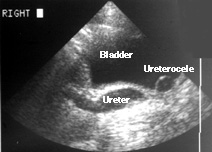

A four-year-old girl has had two urine infections. Her physician ordered the ultrasound seen on the right. Hydronephrosis was seen in the right kidney (image not shown). This is a longitudinal view of the distal right ureter and bladder. The left side of the image (as you face it) is cephalad; the right side is caudal. Notice that the distal ureter is enlarged. Just to the right of the ureter (caudal) a cystic structure lies within the bladder. This is the dilated portion of the distal ureter within the bladder, a ureterocele. The ureter and ureterocele, in fact, are not separated. The ureteric lumen is widened all the way into the bladder, but it is somewhat tortuous so that the ultrasound image, seeing only one plane, seems to show them separated.